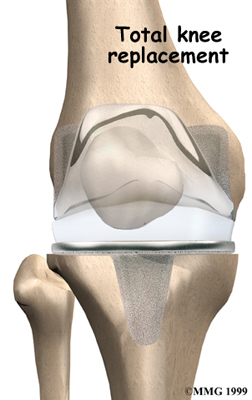

Artificial Knee Replacement

An artificial knee replacement is the ultimate solution for advanced knee OA.

Surgeons prefer not to put a new knee joint in patients younger than 60. This is because younger patients are generally more active and might put too much stress on the joint, causing it to loosen or even crack. A revision surgery to replace a damaged prosthesis is harder to do, has more possible complications, and is usually less successful than a first-time joint replacement surgery.

Related Document: FYZICAL Portland's Guide to Artificial Joint Replacement of the Knee